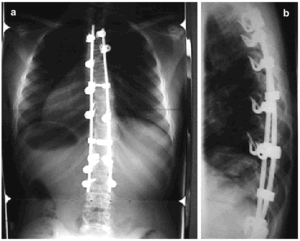

The implants used currently with the same approach have undergone marked changes (third generation implants). The changes introduced have had the aim of producing a repositioning of the thoracic cage that is as anatomically normal as possible by way of a distraction-rotation maneuver. With this technique, applied to elastic thoracic deformities, correction has taken place in the coronal and frontal planes, in the deformity of the rib cage, and in the asymmetry of the thoracic cage (normal kyphosis in the lateral plane, the normal axis in the frontal plane and derotations in the coronal plane) (Figure 4).

Figure 4. X-ray of a scoliotic thoracic spine after surgical treatment, in anteroposterior (a) and lateral (b) views.

Adolescent patients treated by this approach and with third generation implants have experienced improved VC and forced expiratory volume in 1 second. Some authors report that this improvement endures, whereas others have seen it disappear after 1 year.12